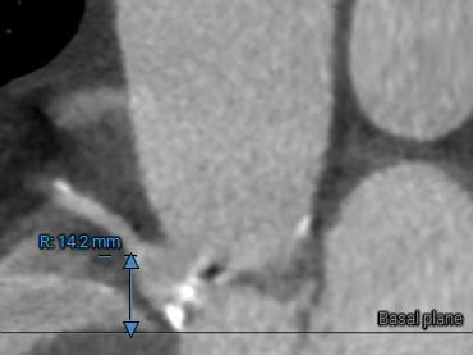

冠脉风险评估

LCA Height

RCA Height